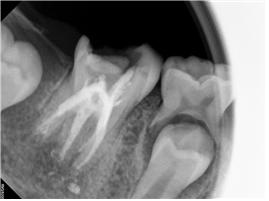

그러고 1년 반이 지나고 24. 01. 11일 사진입니다.

치아 머리는 떼워져만 있고, 제대로 치료되지 못한 치아 하방에는 염증이 가득 차 있습니다.

이 치아는 아이가 평생 써야 되는 영구치입니다.

“과소진료가 최선의 진료는 아닙니다.”

보험재료로 떼웠으니, 좋은 치료가 되는건 아닙니다.

다시 한번 재신경 치료를 권하니, 흔쾌히 치료에 응해주셔서 재신경 치료를 시작합니다.